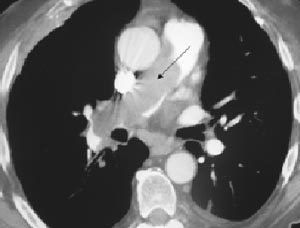

X射線圖本病發病急,須做急救處理。